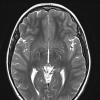

NEOPLASMS (HEMATOLYMPHOID)

Langerhans Cell Histiocytosis (LCH) (9)